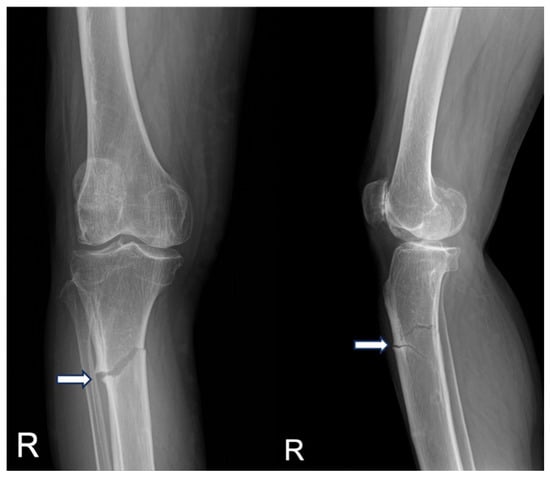

2. Case Presentation